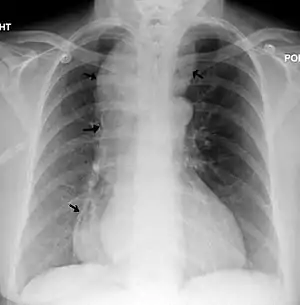

Com a perda do tônus da sua parede muscular e a dificuldade da passagem dos alimentos através da cárdia ocorre progressiva dilatação e alongamento do corpo esofágico, podendo formar uma grande câmara retroesternal contendo grandes volumes de alimento e saliva.

O diagnóstico nas fases iniciais pode ser difícil, já que a dilatação esofágica (mega esôfago) pode ainda não estar presente. Nesses casos os exames de rotina como endoscopia digestiva alta e o RX contrastado do tubo digestivo alto podem ser normais. Com a evolução da doença, o esôfago acaba por se dilatar e aí a endoscopia pode detectar a presença dessa dilatação e de resíduos alimentares retidos no esôfago. Já o RX contrastado de esôfago mostra a dilatação esofágica e nos casos mais avançados o alongamento e tortuosidade do corpo esofágico. Nas fases iniciais quando ainda não se identificam alterações anatômicas significativas, a esofagomanometria é o exame de escolha para o diagnóstico.